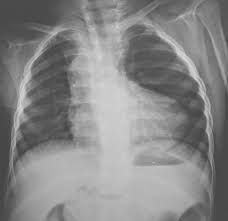

A 'boot-shaped' heart ("cœur en sabot" in French) is the description given to the appearance of the heart on plain film in some cases of Tetralogy of Fallot. It describes the appearances of an upturned cardiac apex due to right ventricular hypertrophy and a concave pulmonary arterial segment.